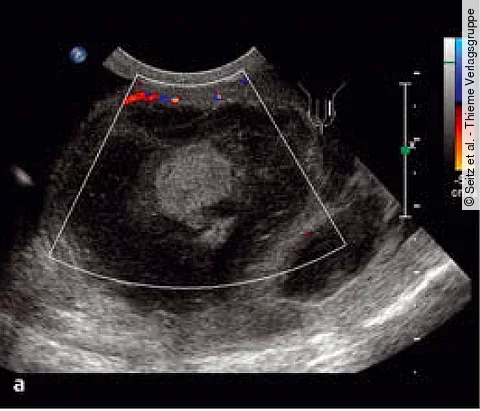

Uro-Quiz der Woche

Auflösung: Hufeisenniere mit weiterer Auffälligkeit

| Auflösung Know-how gefragt!

| News

| Auflösung Know-how gefragt!